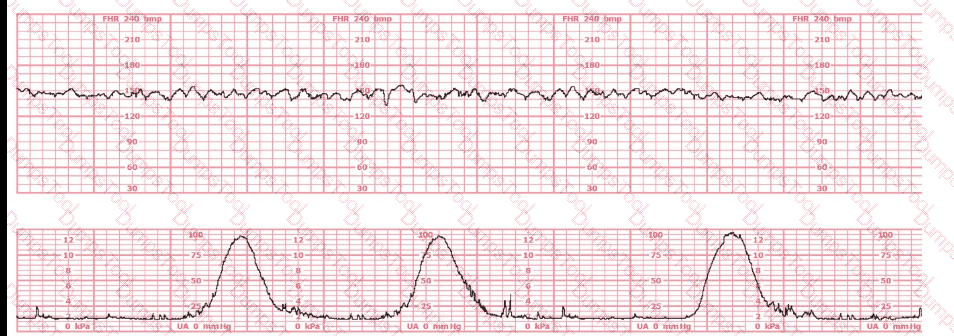

The fetal heart rate tracing shown is obtained upon the woman's admission to labor and delivery. This tracing is most consistent with what maternal condition?

A nulliparous woman at term presents with leaking fluid. Rupture of membranes confirmed. After 6 hours she is completely dilated, +2 station, has been pushing 2 hours with oxytocin at 10 mU/min. The fetal tracing is shown. What is the next step in management?

This fetal heart rate tracing is from a woman in the second stage of labor. This tracing is best interpreted as: